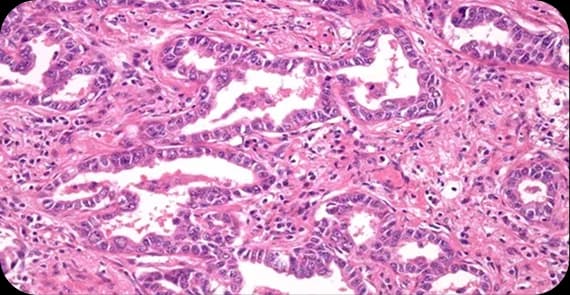

When patients ask what anal cancer is, the explanation begins at the cellular level. Anal cancer occurs when cells lining the anal canal develop genetic mutations that cause uncontrolled growth and division.

What happens in anal cancer is the formation of malignant cells that may invade surrounding tissues or spread to nearby lymph nodes. Unlike colorectal cancer, anal cancer arises specifically in the anal canal tissues.

There are different types of anal cancer depending on the cells involved.

The most common type, arising from the squamous cells lining the anal canal.

Develops from glandular cells near the anus.